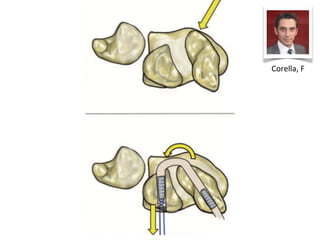

This presentation discusses various topics related to the wrist including static scapholunate ligament dissociation, dorsal ganglion cysts originating from the dorsal capsulolunate septum, treatment of scaphoid pseudarthrosis using a bone graft from the distal radius placed under the extensor tendons, and proximal pole scaphoid pseudarthrosis treated with capitolunate arthrodesis. It also thanks attendees and provides instructions for accessing the presentation online.